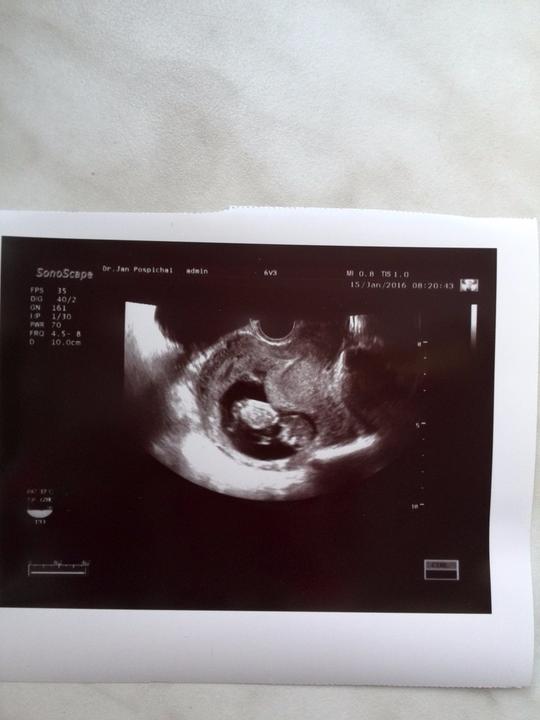

Zdravím Vás dámy 🙂 tak dnes kontrola 20+1tt a už nám potvrdili že budeme 100% chlapák 🙂 fotečku bohužel nemám, mám video ale to netušim jak se sem dává 🙂 vše je v pořádku a rosteme jako z vody... délka od hlavičky k zadečku 15cm a váha 400g... už ted se těšim až náš poklad zase uvidim 🙂